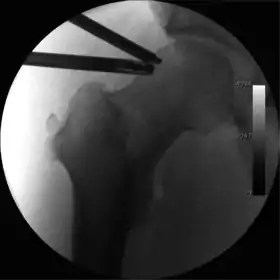

Figure 4. A needle is passed into the joint, breaking the 'suction seal', and allowing further distraction of the hip joint with minimal extra traction

The next step is to insert a fine needle under x-ray guidance into the hip joint. This breaks the 'suction seal' of the joint and allows further distraction if necessary (see fig 4). The surgeon wishes to see the ball move out the socket by approximately 1 cm, so that access to the hip joint can be achieved with minimal risk of damage to the joint surfaces. Most surgeons will inject fluid into the joint at this stage, again to ensure that there is enough space between the ball and socket for safe instrument access. This needle is then removed. The next step is placement of the 'portals', or the small holes made to pass instruments into the joint. This is achieved by again passing a fresh hollow needle into the joint under x-ray control, usually in a slightly different position. The reason for this is so the surgeon can ensure that the needle, and subsequent cannulae do not penetrate and damage the acetabular labrum or cartilage joint surfaces (see fig. 5). Again, surgeons will have their own preferences as to their preferred placement. Through this hollow needle, a long thin flexible guide wire is passed into the joint, and the needle is removed over it, leaving the guide wire in situ. A small cut in the skin is made around the wire, to allow for larger cannulae to be placed over the wire through the portal. The wire therefore guides the larger cannulae into the joint. The most common external diameters of cannulae used are between 4.5 and 5.5 mm. Once the surgeon is satisfied that the cannula is in the correct position, by a combination of feel and x-ray guidance, the guide wire can be withdrawn. Once the first portal is correctly placed, any further portals may be created once the camera is in position, to ensure that they are placed with minimal risk to the joint surfaces. This process can be repeated to gain as many points of entry to the hip joint as the surgeon requires, normally between two and four. Certain of these entry points will be used for the viewing arthroscope and others for operating instruments.